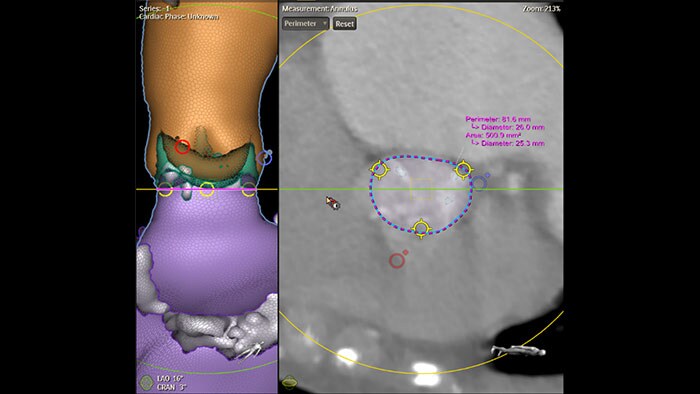

Dimensionamento da TAVR totalmente automatizado com o HeartNavigator